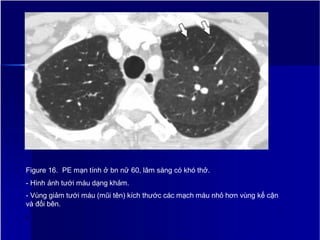

Figure 16. PE mạn tính ở bn nữ 60, lâm sàng có khó thở.

- Hình ảnh tưới máu dạng khảm.

- Vùng giảm tưới máu (mũi tên) kích thước các mạch máu nhỏ hơn vùng kế cận

và đối bên.